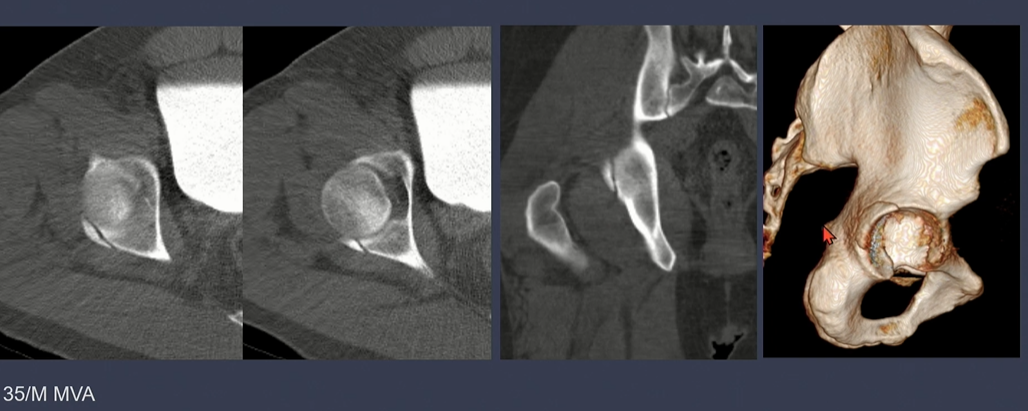

displacement가 없는 경우.

displacement가 있는 경우